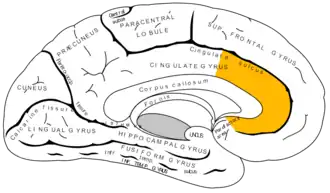

![]() Superficie medial del hemisferio derecho, con las áreas de Brodmann numeradas. | ||

El córtex del cíngulo anterior (CCA) o circunvolución del cíngulo anterior es la parte frontal de la circunvolución del cíngulo, que parece un "collar" formado alrededor del cuerpo calloso, el mazo fibroso que transmite las señales neuronales entre los hemisferios cerebrales derecho e izquierdo. Consiste de las áreas de Brodmann 24, 32, y 33. Parece que juega un rol en una gama amplia de funciones autónomas, tales como regular la presión sanguínea y el ritmo cardíaco, como también para ciertas funciones cognitivas racionales, tales como la inhibición verbal, la anticipación de premio, la toma de decisiones, la empatía[1] y las emociones.[2][3]